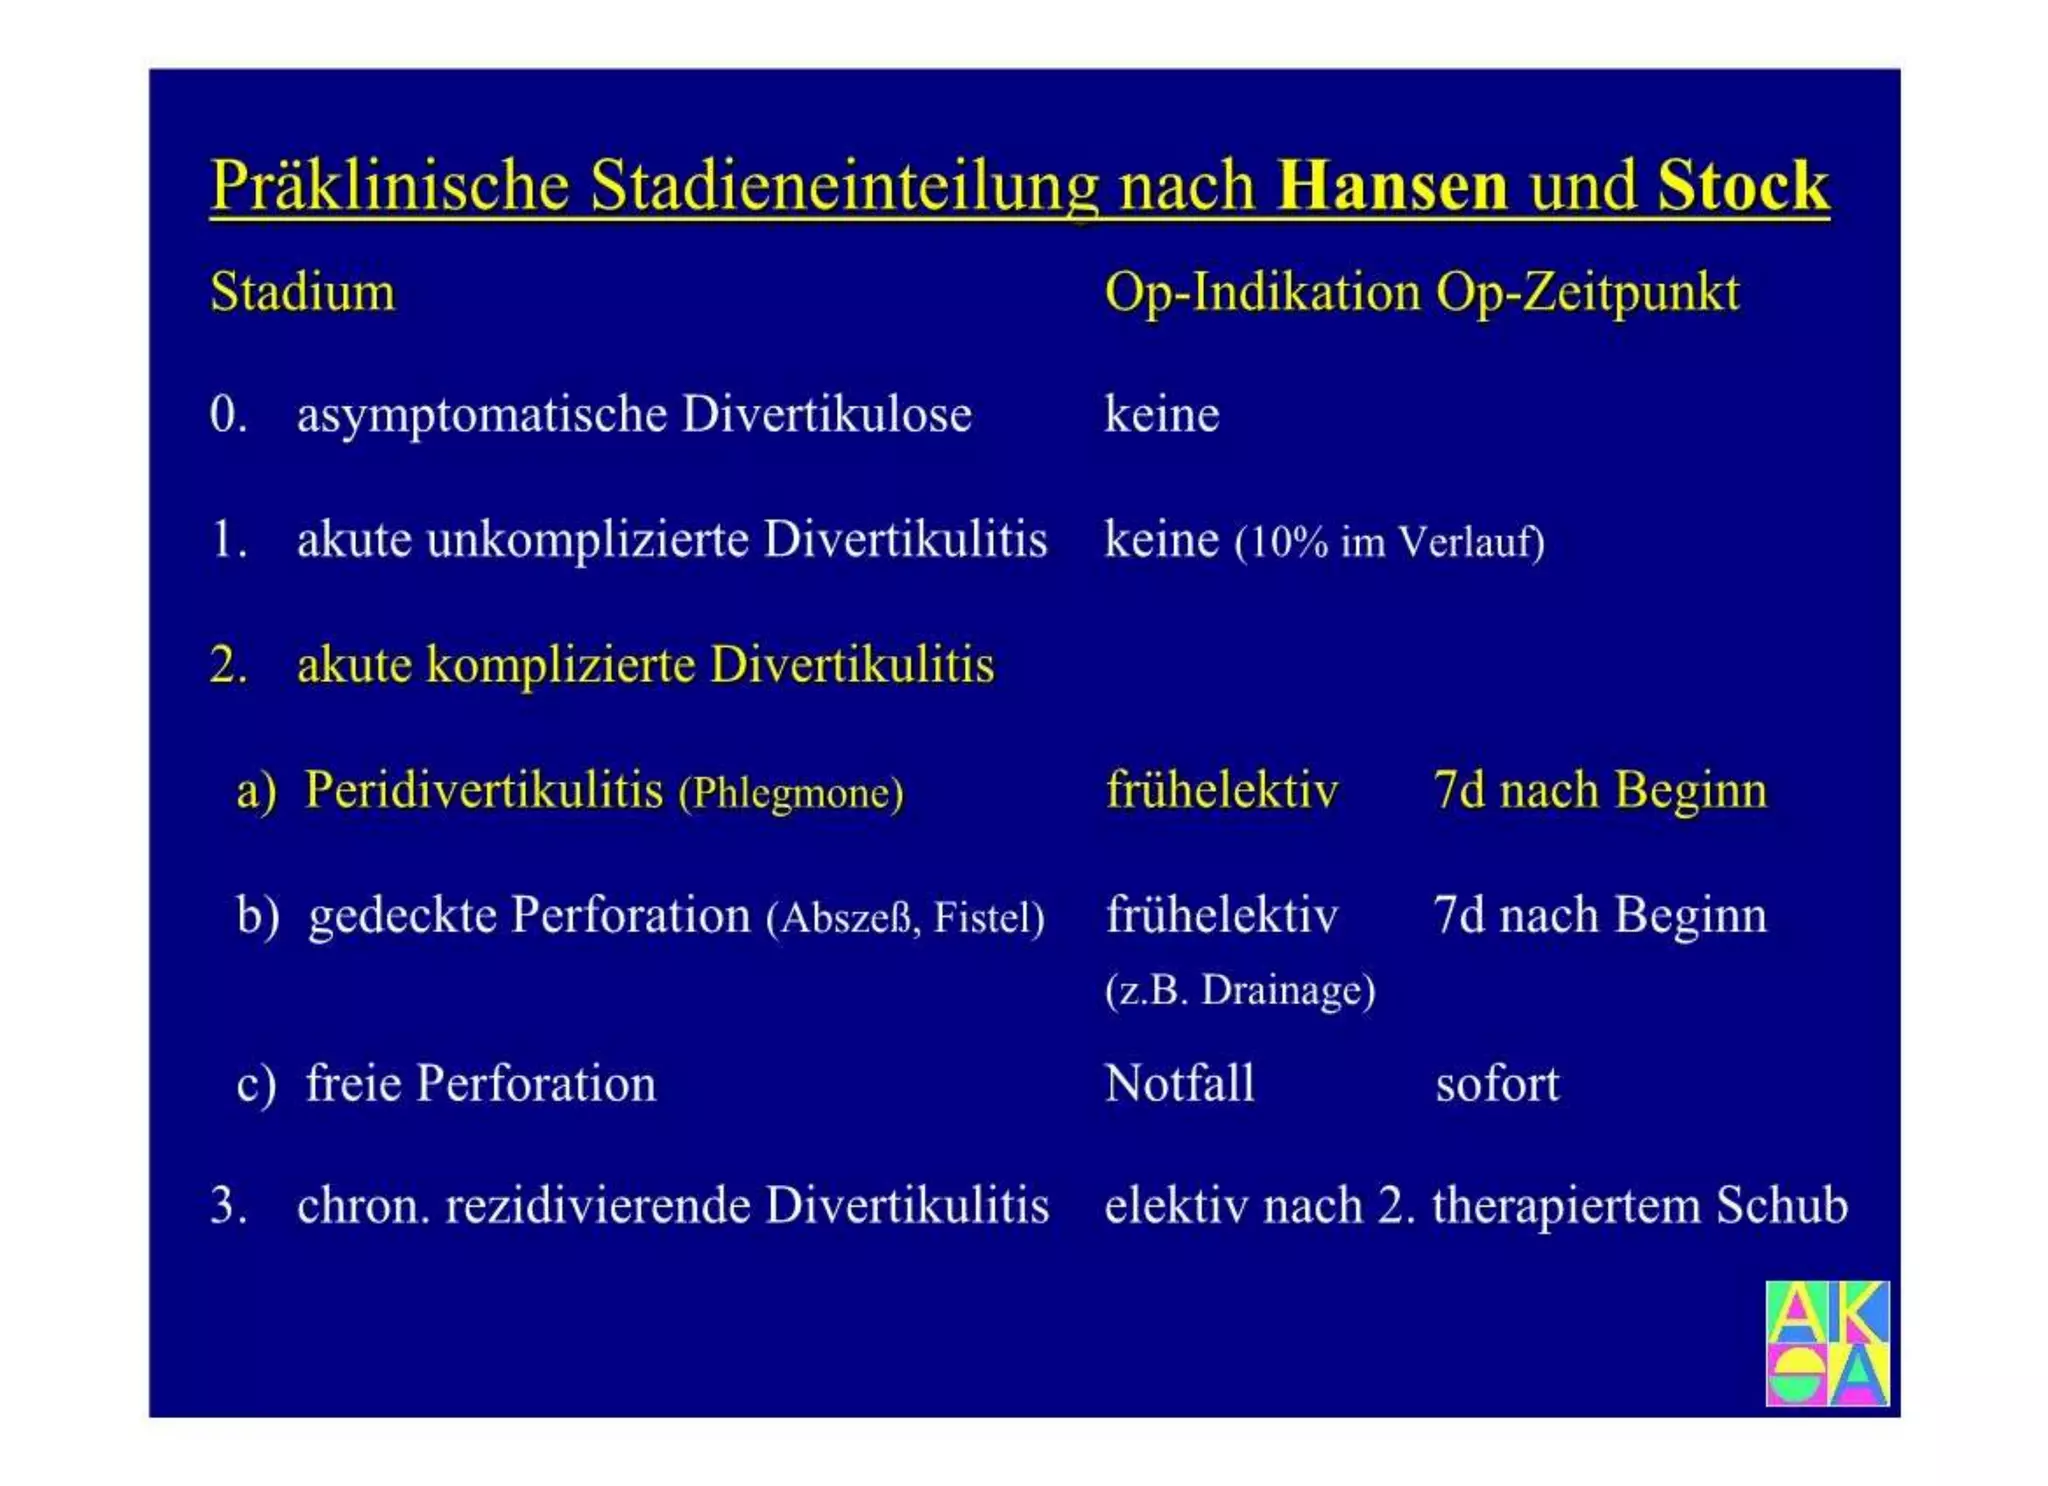

Chronische Enteropathie und Ileus, Dünndarm und Dickdarmdiagnostik, Mechanischer und paralytischer Ileus, Eingeklemmte Darmabschnitte, aufgereihter Bridenileus, und dazu Dickdarmileus, eingeklemmte Hernien, Weitergabeskript